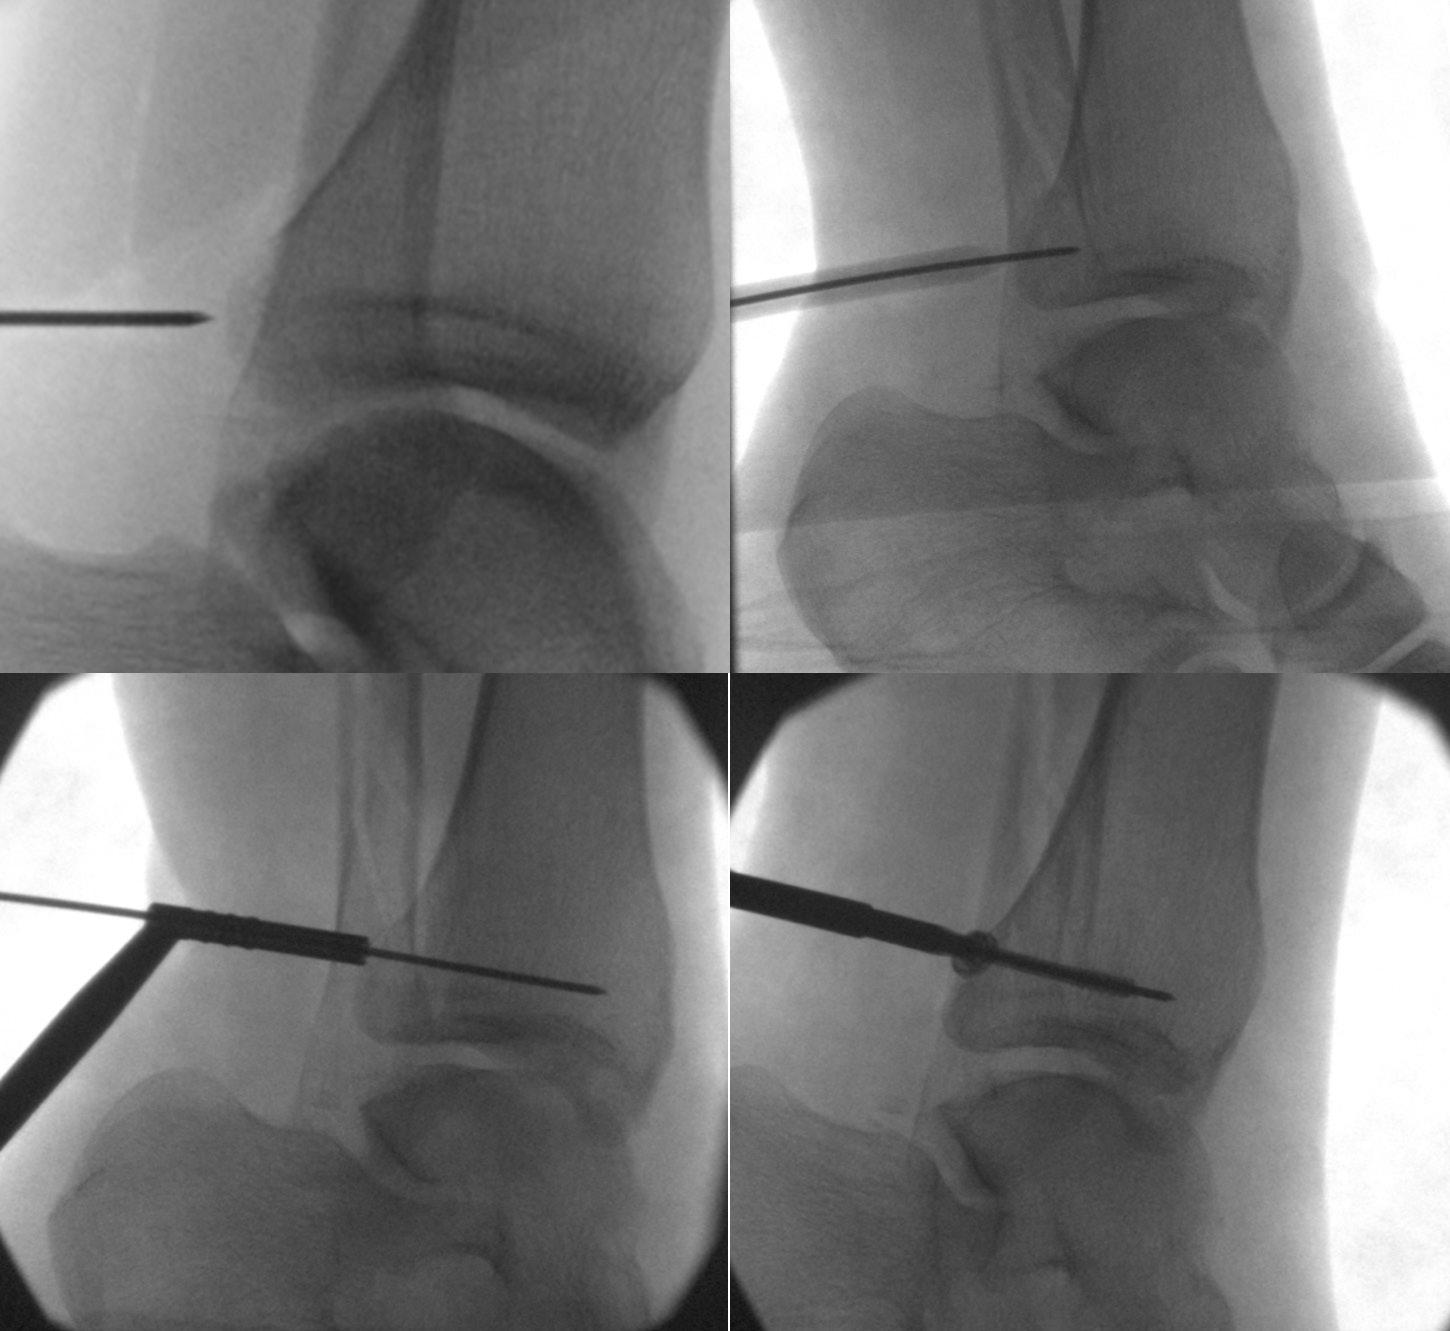

Percutaneous posterolateral malleolus fi xation

Percutaneous posterior to anterior screw fixation enables a safe method of reduction and stabilisation of the posterolateral fragment without the morbidity of a posterior surgical approach. This then frees the surgeon to perform a more favourable direct lateral approach to the fibula for fixation and syndesmotic stabilisation without having to utilise the posterolateral approach and apply metalwork through the peroneal tendon bed.

Technical aspects of case selection, pre-operative planning, patient position, dissection, reduction,

guidewire placement, screw insertion and radiological checks are all pivotal to perform this safely and effectively.

Mildly displaced posterolateral fragments are selected (Haraguchi 1, Mason 1, 2A and Bartonicek 1, 2). Pre-operative CT is obtained to assess the posterior malleolus fracture and screw trajectory.

The patient is positioned in a lateral position with the injured side up and on an elevating block, placed behind the non-operative leg. This gives a lateral view of the ankle and allows external rotation of the hip to enable mortise view fluoroscopy, access to the anterior ankle for trauma scope and access medially for medial malleolus fixation. Anatomy is marked on the skin using image intensifier and the level of incision is planned to approach the posterior malleolus.

The posterior malleolus should be fixed first to enable proper assessment of joint line and fracture fragment reduction. Once medial and lateral metalwork is in situ this will obscure fluoroscopic assessment of the posterior malleolus. If fibula reduction is required to restore the syndesmosis prior to posterior fixation the fibula can be approached through a direct lateral approach in this position, reduced and held with a clamp or K-wire in a manner that doesn’t obscure fluoroscopic assessment.

A 10mm incision on the lateral edge of the Achilles tendon at the level of the

posterior malleolus and a 10mm tunnel is blunt dissected down to bone using long dissecting scissors. The leg is rotated until the X-ray projection of the posterior malleolus cortex is separate to the posterior cortex of the fibula. A radiolucent depth gauge or 2mm syringe barrel is used as a wire guide to protect the soft tissues. A guidewire is placed on the posterior malleolus cortex by feel and the leg rotated until there is no overlap between cortex and wire to help judge the exact position in relation to the fracture

and to check the wire is on the tibial cortex and not the fibula.

The guidewire is passed into the fragment and the position is checked on the AP image. The fibula is reduced into the incisura with thumb pressure. The leg is then rotated until the fracture plane is visible on fluoroscopy. The depth gauge/ syringe and guidewire are used to joystick the fragment into position and the wire is passed across the fracture. If the fragment requires further inferior translation

the wire can be angled inferiorly so that screw compression will translate the fragment distally. Once the wire is across the fragment, the depth gauge is pushed against the posterior malleolus to check the fragment will compress. Wire position is checked on the mortise view with depth gauge or artery clip against the posterior tibial cortex to assess the exact entry point, ensuring it will not irritate the fibula or syndesmosis.

The near cortex only is drilled, and one unicortical 4mm cannulated partially threaded screw and washer is inserted under image intensifier. As the washer meets the posterior malleolus it should angle to meet the cortical contour of the posterior malleolus, further confirming correct positioning, and the fracture should be seen to compress. If the wire has been angled inferiorly the fragment should reduce more distally by 1mm or so. Final checks are performed, and the percutaneous portal can be closed with skin suture alone. The surgeon is then free to complete necessary fixation of the malleoli and syndesmosis through direct approaches. n